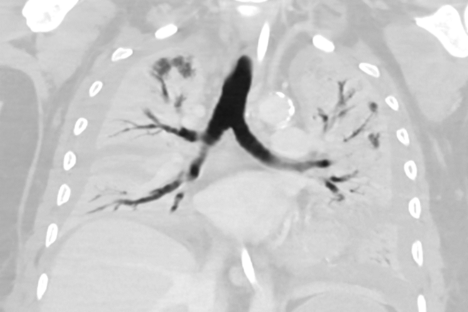

• Erhebung der Bildcharakteristika von Patientinnen und Patienten mit respiratorischem Infekt / COVID-19 - eine Registerstudie

Prüfzentrum: Universitätsklinik für Radiologie und Nuklearmedizin

Verantwortlicher Prüfarzt: Herr Assoc. Prof. Dr. Helmut Prosch